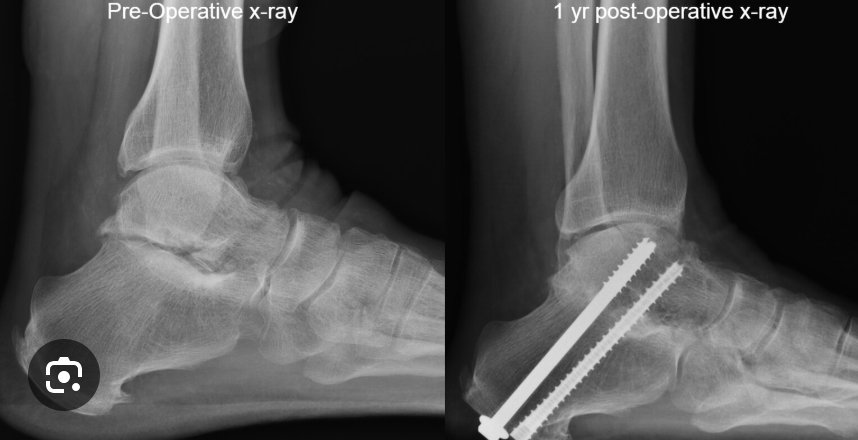

Example of sub-talar fusion

Subtalar Fusion

This surgery fuses or connects the talus bone with the calcaneus bone. This joint is then effectively gone, taking away the ankles ability to dorsiflex, or bring the toes toward the shin. This is a critical motion for walking, running, and creating motion at the foot and ankle.